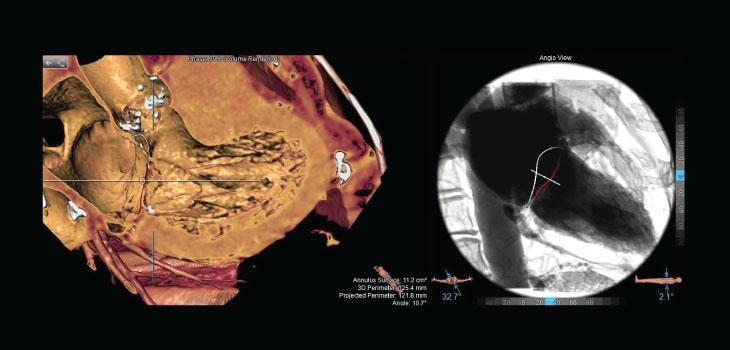

The Septal Crossing workflow enables visualization of cardiac structures in a simulated angioview. In this simulated angioview, anatomic relations between the interatrial septum, left atrial appendage (LAA) ostium, mitral annulus and vena cava can be easily determined.